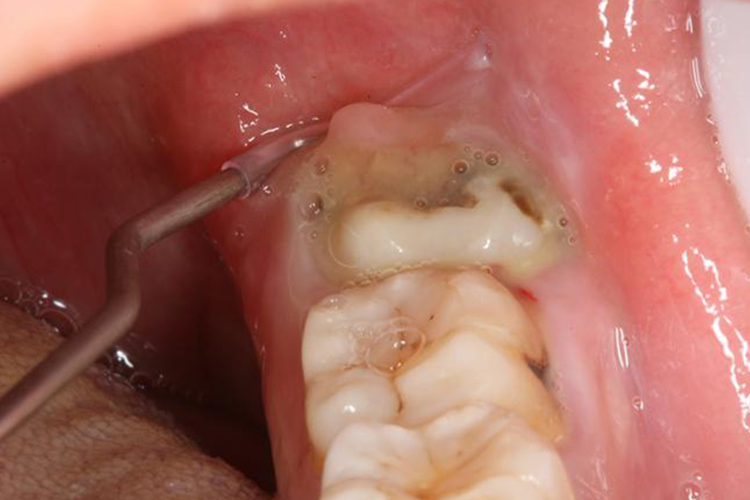

智齿冠周炎急性发作时会出现龈瓣红肿、压痛,在挤压时出现食物残渣和脓性物。

常表现为阻生牙牙冠上覆盖的龈瓣红肿、压痛,挤压龈瓣时,常有食物残渣或脓性物溢出,龈瓣表面常可见到咬痕。反复发作者,龈瓣可有增生。